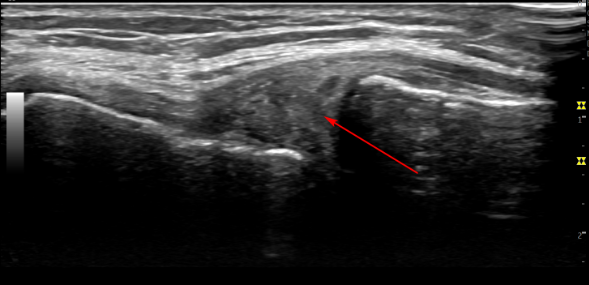

8개월 치료 후

8개월 치료 후에음곡혈에서 촬영한경혈 초음파 영상**입니다.

연골 파열로 인한 반월판 낭종(노란색 화살표)이

변화된 것이 보이시나요??

하지만 손상된 연골은 완전히 회복되지 않기 때문에

앞으로도 꾸준한 관리가 필요합니다.